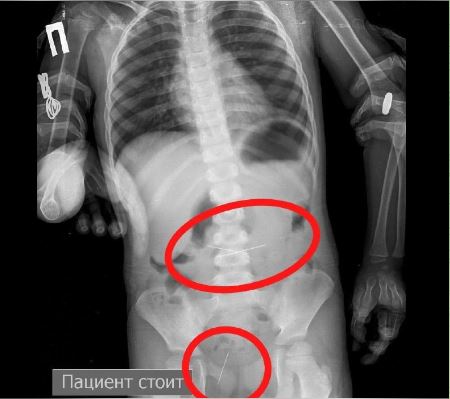

— На контрольной R–грамме брюшной полости обнаружены еще 2 иглы в верхнем этапе брюшной полости и 1 игла в проекции таза. Проведена повторная ЭФГДС и удалена игла из желудка. Затем при помощи колоноскопии удалена игла, фиксированная в сигмовидной кишке, — сообщил врач-хирург высшей категории Сейдахмет Чинибеков.

Ребенок продолжал находиться под наблюдением. На контрольной R–грамме брюшной полости обнаружена четвертая игла в проекции таза. Проведена колоноскопия и из сигмовидной кишки удалена последняя игла, которая концом была фиксирована в слизистую кишечника.